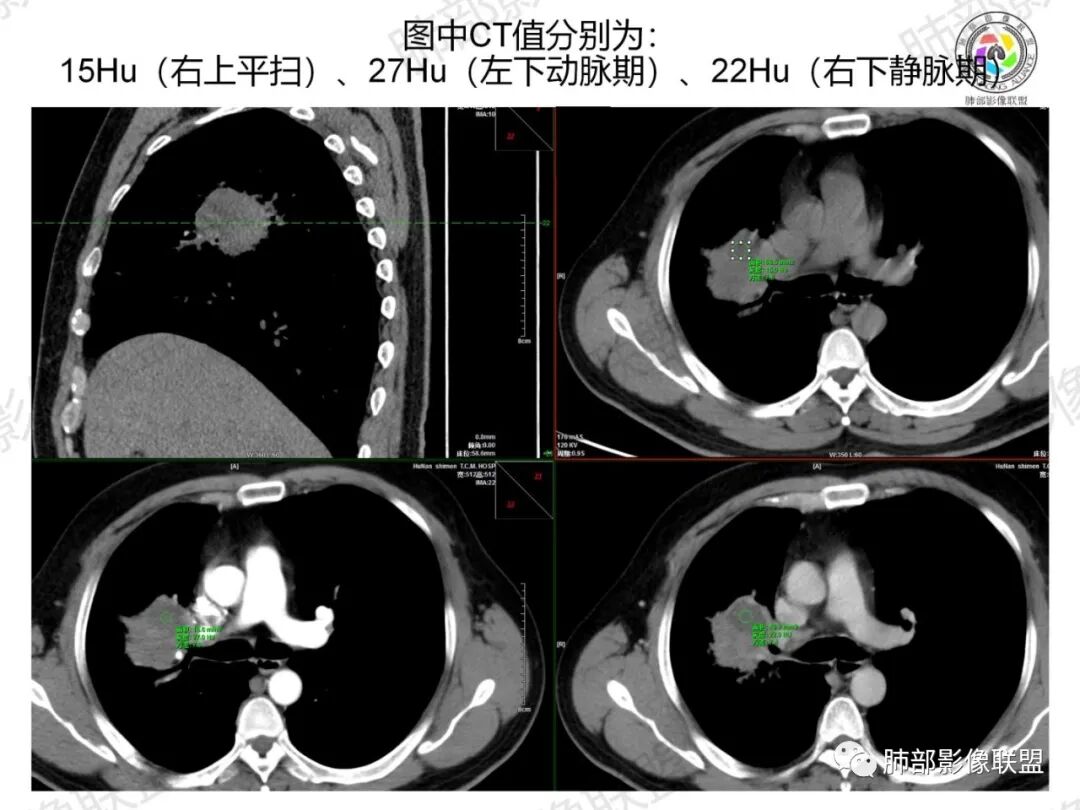

了:中年男性,右肺门肿块影,浅分叶,周围晕征,边缘清楚,小叶间隔增厚,树芽征,支气管截断,不均匀强化,内可见低密度坏死,纵隔淋巴结肿大,综合考虑肺部肿瘤并阻塞性肺炎

一切∮随缘:右肺门肿块影形态不规则,边缘毛糙,右肺上叶支气管堵塞,病变跨叶生长,远端血管束增粗,周围散在多发结节,部分位于胸膜下,平扫密度尚均匀,增强后不均匀强化,呈中度强化,坏死区无强化,纵隔淋巴结肿大。临床无感染症状,考虑恶性,鳞癌,腺癌,鉴别慢性脓肿。

那个人:中年男性,右肺肿块影,支气管截断,截断口非圆盾,病灶膨隆分叶,坏死,强化。病灶内血管破坏。病灶远端树芽及小结节影,考虑恶性,鉴别结核

周太狼:中年男性,吸烟史,陈旧结核史,呼吸道症状未提及,抗感染治疗无效。影像见右上肺门区软组织肿块影,浅分叶、毛刺,支气管似有截断,其内密度不均匀,不均匀强化,内可见低密度坏死区,病壮周围见斑片、结节影。纵隔内淋巴结稍肿大,首先考虑恶性,肺部肿瘤并阻塞性肺炎,肺鳞癌可能,鉴别结核。

弹指之间:中年男性,结核史、吸烟;右肺门肿块,特点:右肺上叶尖、前段支气管狭窄、部分阻塞(肿块大、支气管狭窄闭塞相对轻),肿块内血管部分残留(生长速度快,浸润>破坏),周围见渗出、炎症,部分实变;内见坏死、位于边缘区域;纵隔淋巴结肿大;考虑恶性,1.非支气管粘膜起源首先考虑,淋巴瘤?(但坏死相对多了);2.鳞癌(支气管阻塞轻);3.小细胞待排。

浅分叶,内部坏死部分边界不清,实性部分明显强化